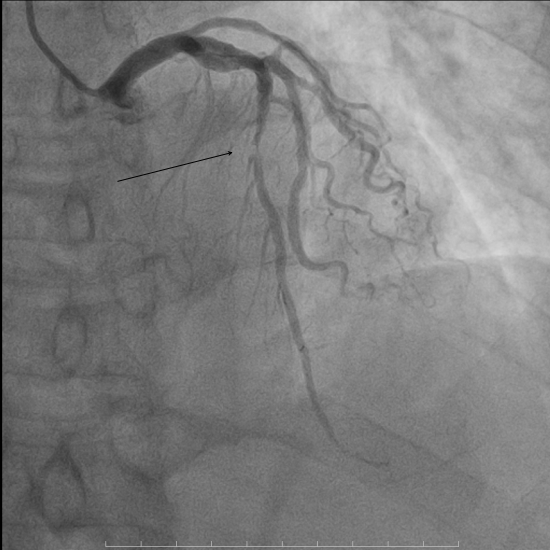

术前心电图同样反映出该病症的相关特征。入院后急诊冠脉造影发现,前降支近段存在50%局限性狭窄,中段节段性病变,且最重狭窄达到90%并可见明显的血栓影。为更精准把握血管内部情况,我院团队进一步行血管内超声检查,结果显示前降支中段可见纤维脂质斑块,最小管腔面积仅为2.11mm²,斑块负荷高达81.5%。面对如此复杂的病情,我院介入团队沉着冷静、有条不紊地开展救治工作,先进行球囊扩张,而后成功植入一枚3.0*30mm支架。术后再次通过血管内超声检查确认,支架贴壁、膨胀良好,最小管腔面积已提升至6.15mm²,手术结果十分满意,患者胸痛症状明显缓解。

▲术后冠脉造影